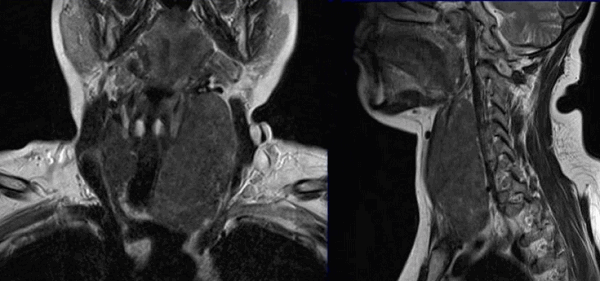

Метастазы на снимках МРТ шеи

Врач-рентгенолог указывает в описании признаки злокачественного образования щитовидной железы, но окончательный диагноз ставят на основании дополнительных исследований (биопсии, клинических анализов и пр.)

Новообразование в области щитовидной железы